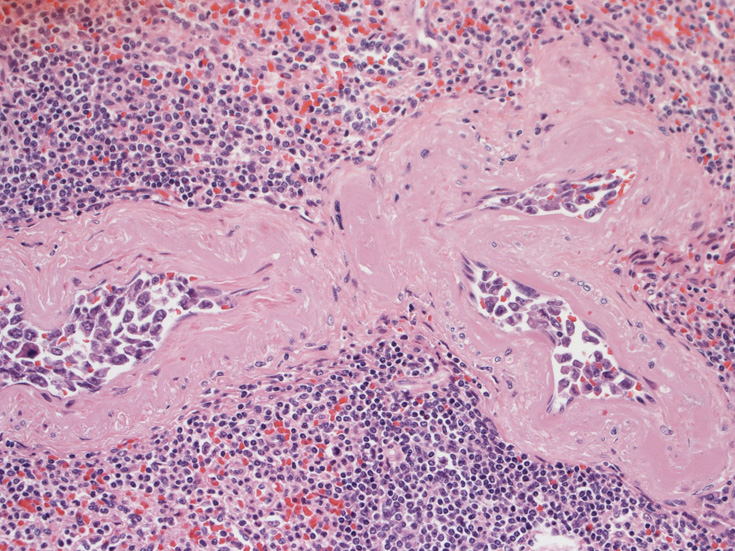

肺B;小気管支動脈, 肺動脈内を腫瘍細胞が閉塞する. 動脈内膜に浸潤性増殖している(B)。